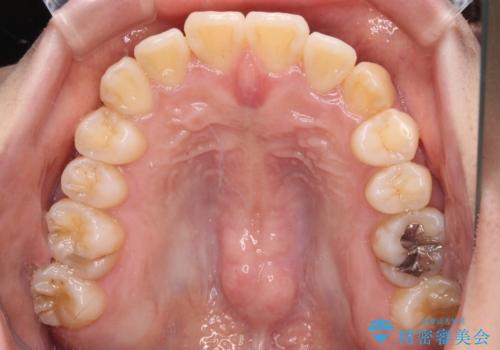

- 八重歯や前歯の捻転とクロスバイトが気になり、インビザラインによる矯正治療を希望して来院された患者様です。

上顎側切歯(上の真ん中から2番目の歯)が舌側転位している場合、無理して動かそうとすると歯髄壊死を起こすリスクが高い印象があります。

インビザライン単体でも治療は可能ですが、安全策としてインビザラインで歯列を移動する前に上顎前歯をワイヤー矯正で整え、その後上下歯列をインビザラインにて矯正治療を行うこととしました。

舌側転位している側切歯特有の、切縁の位置が不揃いであったり、根元が内側に引っ込んだ状態であったりという、インビザライン独特の仕上がりになることなく、きれいに整った歯列とすることができました。